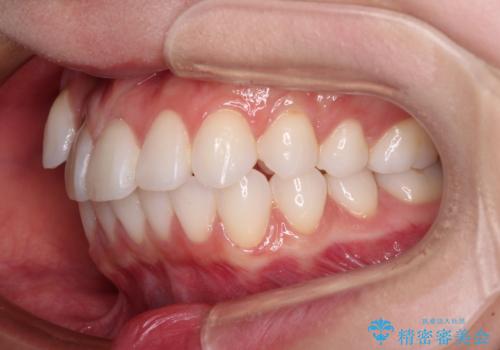

奥歯の咬み合わせを維持しながら正中位置を改善するために、補助装置を使用しました。

予定より期間がかかりましたが、上下の正中位置を綺麗に一致させることができました。